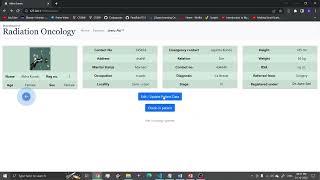

Second Opinion (Второе мнение) by Abduvakhob Sodikov

Prototype of a web application for registering patients who want to get a second opinion on CT or MRI studies from other medical organizations